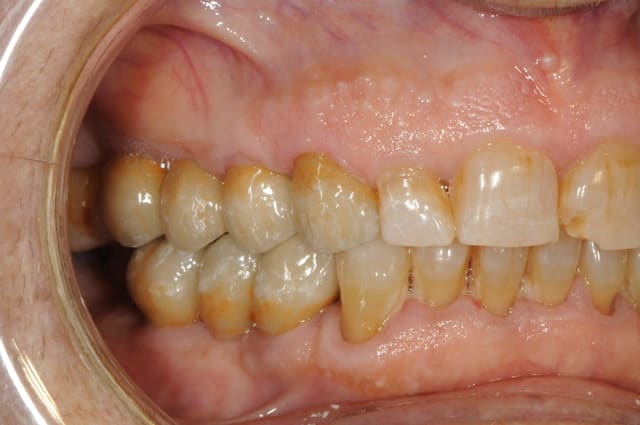

plus sérieusement mais suffisamment imparfait pour qu'on puisse trouver...

Kem inf ap neluwo - Eugenol

Kem sup2 ap bamol9 - Eugenol

pour faciliter le chmilblick : sur une arcade il y a une seule prothèse visible et sur l'autre il n'y a qu'une seule dent naturelle visible

il s'agit d'un mix de facettes et couronnes céramo-céramiques

32 et 23

bravo Henri